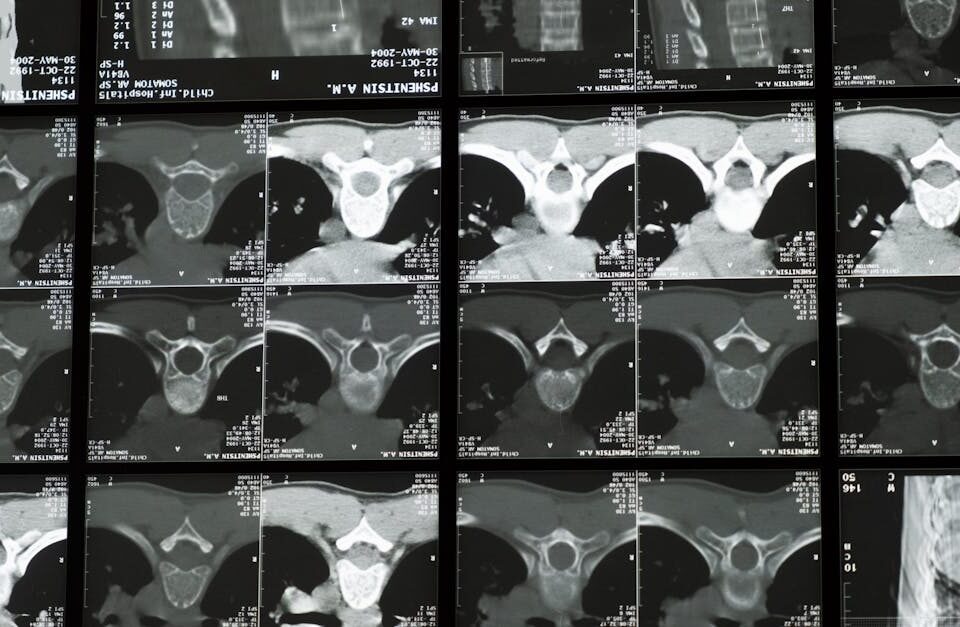

Est-il nécessaire d’effectuer des examens avant de commencer la décompression neurovertébrale?

Oui, des examens comme une IRM ou des radiographies sont souvent recommandés pour évaluer l’état de la colonne.